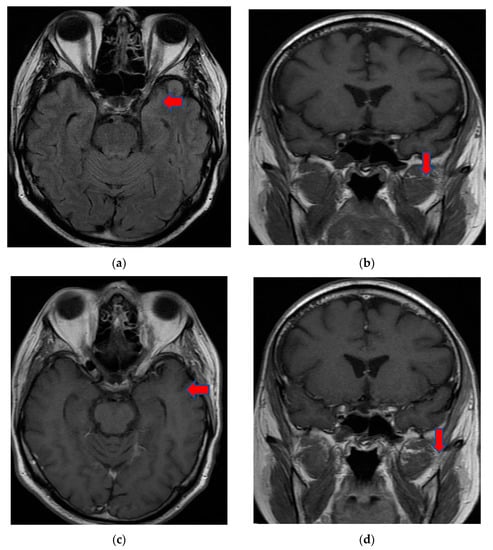

On day eight, the patient became comatose with altered neurological status and was intubated, with mechanical ventilation in the intensive care unit. He required i.v. fluids, pressors, ceftriaxone, vancomycin, and antifungals due to concerns regarding sepsis. A CT of the brain was obtained in light of the acute hemorrhage of intraparenchymal fronto-parieto-temporal lobes, showing important edema (Figure 4).

Figure 4.

(a,b), Brain-CT showed acute hemorrhage of intraparenchymal fronto-parieto-temporal lobes with important edema and ventricular extension.